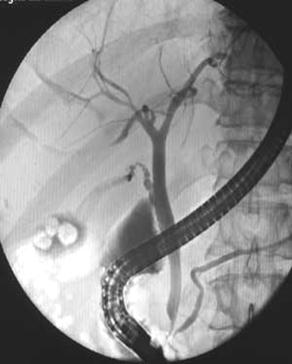

Рисунок 6 – ЭРХПГ: А – камни в желчном пузыре без патологии протоков;

Б – картина холедохолитиаза (расширен холедох, визуализируются конкременты)